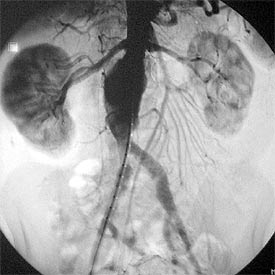

Un equipo multidisciplinar del Complejo Hospitalario Universitario de Albacete (CHUA) ha realizado con éxito una intervención quirúrgica para tratar un aneurisma de aorta renal de alto riesgo mediante endoprótesis fenestrada -con dos agujeros o ventanas- para arterias renales. La operación, que supone la única opción para pacientes que por la patología asociada que sufren no soportan la cirugía tradicional, duró cinco horas y tuvo lugar el pasado 15 de enero en el hospital de Albacete. El paciente fue capaz de caminar y comer 24 horas más tarde.

Sin embargo, como explica Alberto Masegosa, jefe de la Unidad de Angiología y Cirugía Vascular del CHUA y responsable de la intervención, "las condiciones del paciente intervenido, de 59 años, suponían un elevado riesgo para su salud en caso de cirugía estándar, pues padecía cardiopatía isquémica severa con enfermedad de tres vasos no revascularizable y episodios de angina inestable, y había sido sometido a cirugías previas en el abdomen por colitis ulcerosa". Además, el diámetro del aneurisma era de 6,5 centímetros y, por estar demasiado próximo al riñón, no había zona sana donde sujetar una endoprótesis convencional.

"Esta novedosa técnica", continúa Masegosa, "es una modificación más laboriosa que la ya de por sí compleja endoprótesis estándar. Hasta ahora, las endoprótesis se realizaban en zonas de la aorta sin ramas que irrigaran órganos vitales. La fenestración -dos orificios en la propia prótesis- permite incluir segmentos de aorta con ramas a estos órganos, como los riñones, para mantener la circulación y evitar el fallo de éstos. Además, la prótesis se puede anclar por encima de los riñones, aunque no haya zona sana donde sujetarse. Ésta se realiza a medida para cada paciente y se introduce a través de las arterias femorales mediante una pequeña incisión en las ingles y, al llegar al aneurisma, se despliega.

Es una técnica selectiva reservada a pacientes de alto riesgo quirúrgico que no son candidatos a la cirugía estándar, que sigue siendo la primera técnica de elección. El éxito de la intervención abre una puerta a este tipo de pacientes, cuyo índice de mortalidad es muy elevado sin endoprótesis. La implantada en Albacete va fijada con un stent de acero similar a los coronarios recubierto de material textil que evita que la presión de la sangre provoque la rotura del aneurisma.